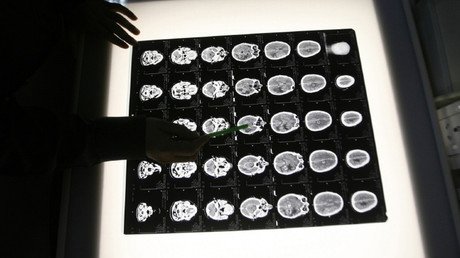

Para su estudio, los investigadores analizaron 904 tumores de 14 tipos de cáncer y descubrieron que la evolución de 323 tumores, incluidos de estómago, intestino y algunos cánceres de pulmón, podían predecirse mediante la aplicación de este modelo.